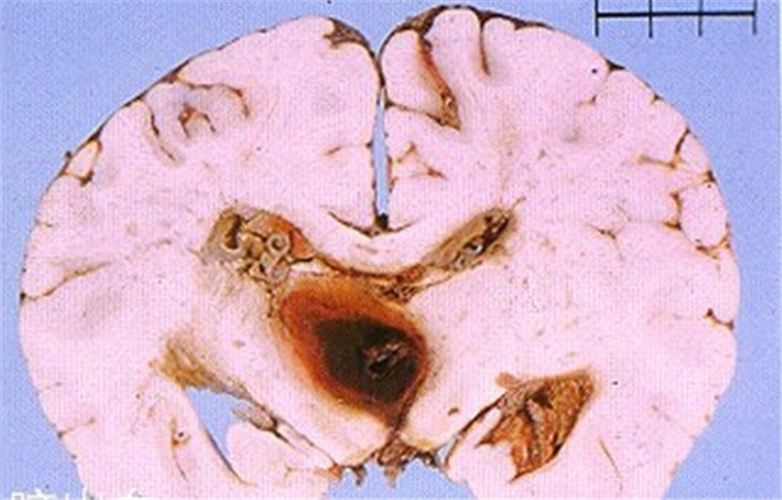

腦血塊導致腦血管痙攣切片

腦血栓導致腦血管痙攣治療